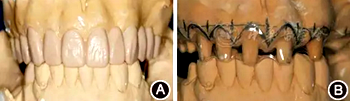

(1)制作診斷蠟型:牙齦炎癥控制后,取研究模型,以上前牙中齦緣水平最高者為參考點(diǎn),根據(jù)理想牙齦曲線形態(tài)、牙齦頂點(diǎn)位置及牙齦線協(xié)調(diào)對(duì)稱關(guān)系,擬定修復(fù)體邊緣和齦緣位置。結(jié)合上中切牙理想大小、形態(tài)、寬長(zhǎng)比及恰當(dāng)?shù)慕佑|區(qū)長(zhǎng)度制作診斷蠟型,模擬修復(fù)效果,根據(jù)診斷蠟型和術(shù)前照片,與患者溝通、結(jié)合其意見修改蠟型,確定最終修復(fù)體形態(tài)及齦緣位置(圖4A)。

圖4 術(shù)前制作診斷蠟型及手術(shù)導(dǎo)板 A:診斷蠟型,確定最終修復(fù)體的形態(tài)及齦緣位置;B:透明墊式手術(shù)導(dǎo)板,用以指導(dǎo)手術(shù)切口的精確控制